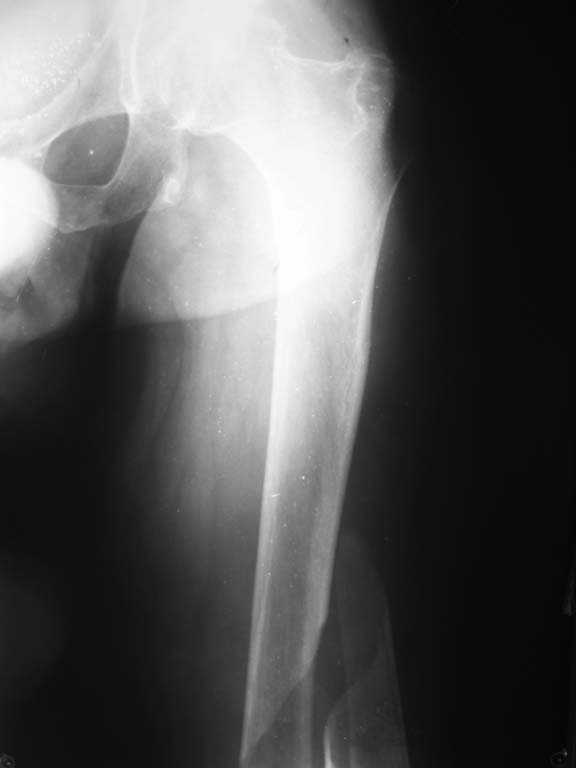

В отделение поступил больной 54 лет. Диагноз:закрытый перелом правой бедренной кости в/3 со

смещением, закрытый перелом левой бедренной кости в с/3 со смещением.Посттравматическая

клиновидная деформация тела Th11 позвонка(травма в 1991г),плегия н/конечностей,

нарушение функции тазовых органов. Травму получил при пересаживании из коляски на кровать.

Обследован, выявлены изменения в моче характерные для этой категории больных.Учитывая

сопутствующую патологию и остеопороз планируем блокируемый остеосинтез стержнями

максимального диаметра, соответствующих диаметру костно-мозгового канала. Уважаемые

коллеги!Кто имеет опыт лечения данной травмы, пожалуйста, поделитесь возможными

вариантами лечения.